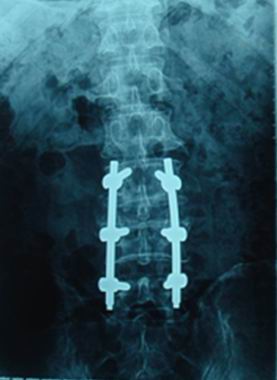

金属所沈阳材料科学国家(联合)实验室工程合金研究部杨锐、郝玉琳等研制的Ti2448新型医用钛合金于5月28日获美国专利授权(US 7,722,805)。另外,采用Ti2448合金制做的骨科用接骨板和脊柱固定系统两类植入器件已在数家医院完成临床试验,进入规模应用阶段。

中国科学院金属研究所自2005年起与威高骨科材料有限公司合作,先后开展了植入器械的研发和产品注册证的申报工作。2006年,金属所建立了Ti2448合金材料的企业标准,威高骨科采用Ti2448合金加工了弹性接骨板和脊柱固定系统,并分别报送国家食品药品监督管理局天津医疗器械监督检验中心检验,2008年成功通过了生物学安全性考核。2008年和2009年,Ti2448合金接骨板和脊柱固定系统分别在山东大学附属齐鲁医院、山东省中医院以及中国医科大学附属第一临床医院、吉林大学附属第二临床医院开展了临床试验。目前,两类产品的临床试验已经成功完成,威高骨科材料有限公司已经向国家食品药品监督管理局申报产品注册证。